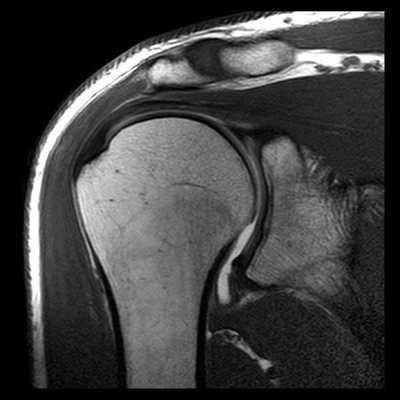

МРТ плечевого сустава. Корональные Т1-взвешенные МРТ. Переломы Хилла-Сакса и Банкарта.

КТ плечевого сустава, Переломы Банкарта и Хилла-Сакса.

МРТ плечевого сустава с подавлением сигнала от жира. Т2-взвешенная корональная МРТ. Перелом большого бугорка (стрелка).

При МРТ плечевого сустава косвенным признаком разрыва вращательной манжеты служит высокий сигнал на Т2-взвешенных от поверхности сустава до субакромиальной (субдельтовидной) сумки. Частичные разрывы чаще всего по передней поверхности сухожилия м.supraspinatus, реже примыкая к большой бугристости или сухожилия м. infraspinatus.

МРТ плечевого сустава. Т2-взвешенная корональная МРТ. Субакромиальное скопление жидкости - косвенный признак разрыва вращательной манжеты.

МРТ плечевого сустава. Т1-взвешенная корональная МРТ. Частичный разрыв вращательной манжеты.

МРТ плечевого сустава. Т2-взвешенная корональная МРТ. Передний разрыв вращательной манжеты